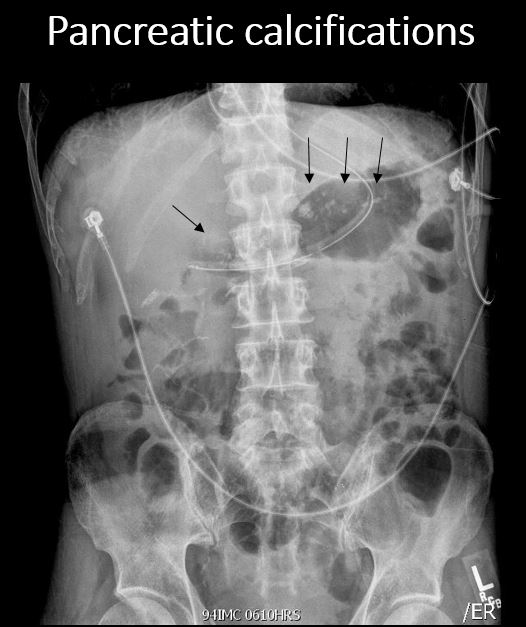

There are calcifications in the pancreas. |

No | NA |